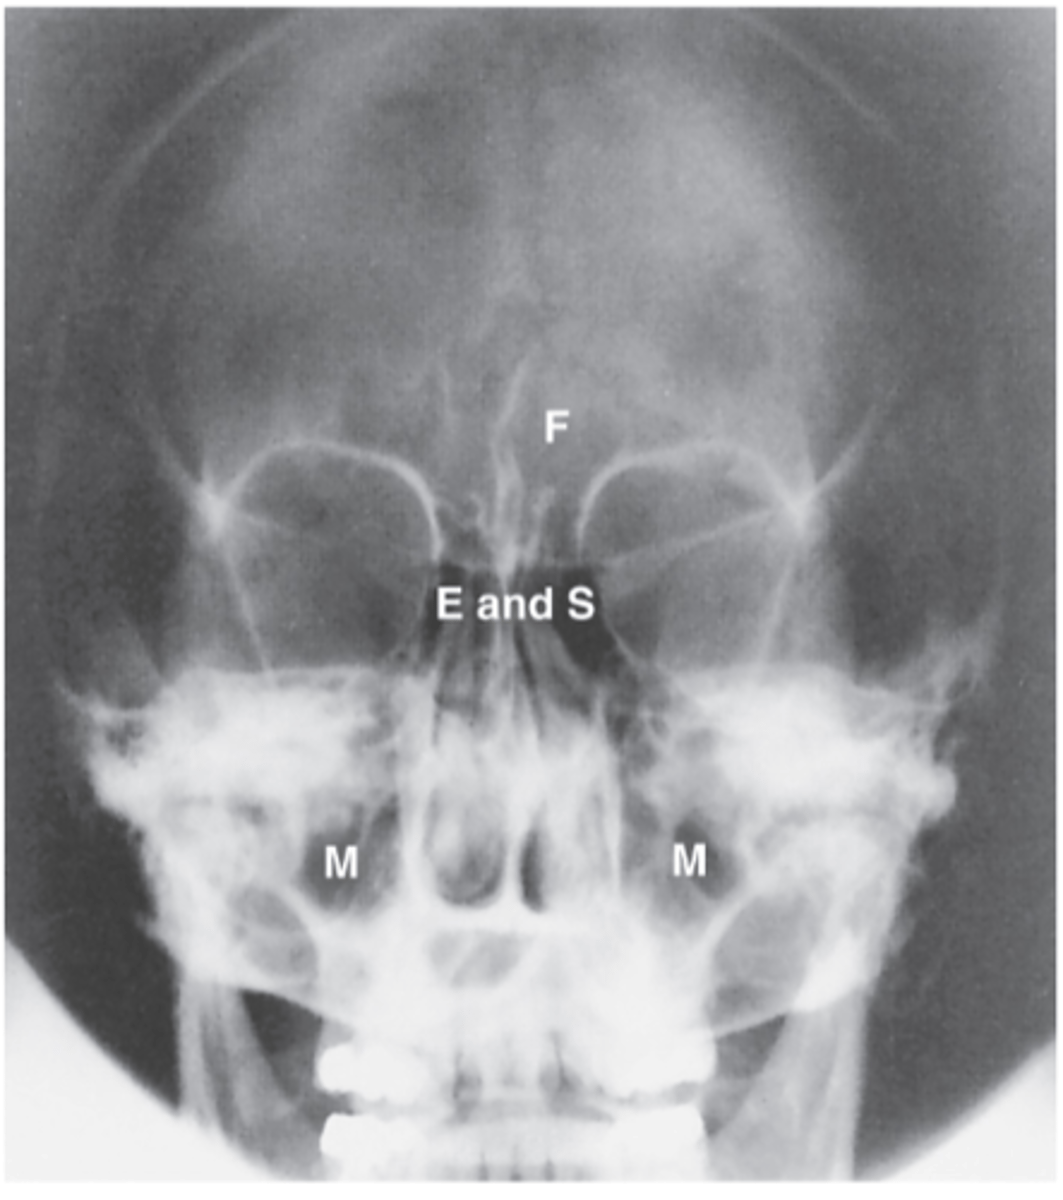

Ethmoid Sinus

E

Sphenoid Sinus

S

Maxillary Sinus

M

Frontal Sinus

F

Lateral Sinuses

What projection is this?

Midway between the EAM and the outer canthus

What is the CR for Lateral Sinuses?

Ethmoid

Sphenoid

Frontal

Maxillary

What sinuses are demonstrated on a Lateral sinuses radiograph?

Interpupillary line (IPL)

What line should be perpendicular to the IR for Lateral Sinuses?

Midsagittal plane (MSP)

Orbitomeatal line (OML)

What lines should be parallel to the IR for Lateral Sinuses ?